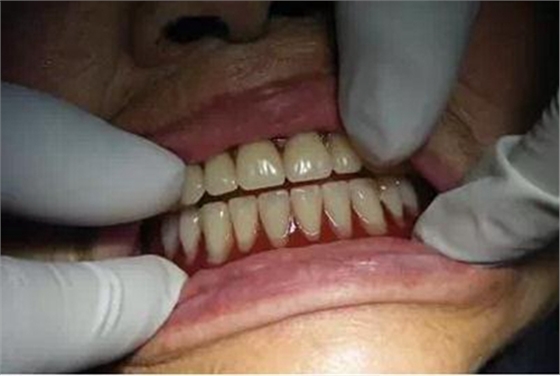

這是我修復(fù)的一例牙槽嵴低平患者,采用的是滬鴿公司出品的無(wú)尖牙。

患者戴入后的穩(wěn)定性很好。

但患者總感到義齒咀嚼效率不高,吃飯時(shí)下頜黏膜常常疼痛。讓患者復(fù)診,患者說(shuō)她戴了幾十年的假牙,這點(diǎn)事情自己就搞定了,用刀子修改后就不再?gòu)?fù)診了。(不建議患者自己修改處理。)

同患者的家屬進(jìn)行了回訪,感到患者在使用中還是不太滿(mǎn)意。